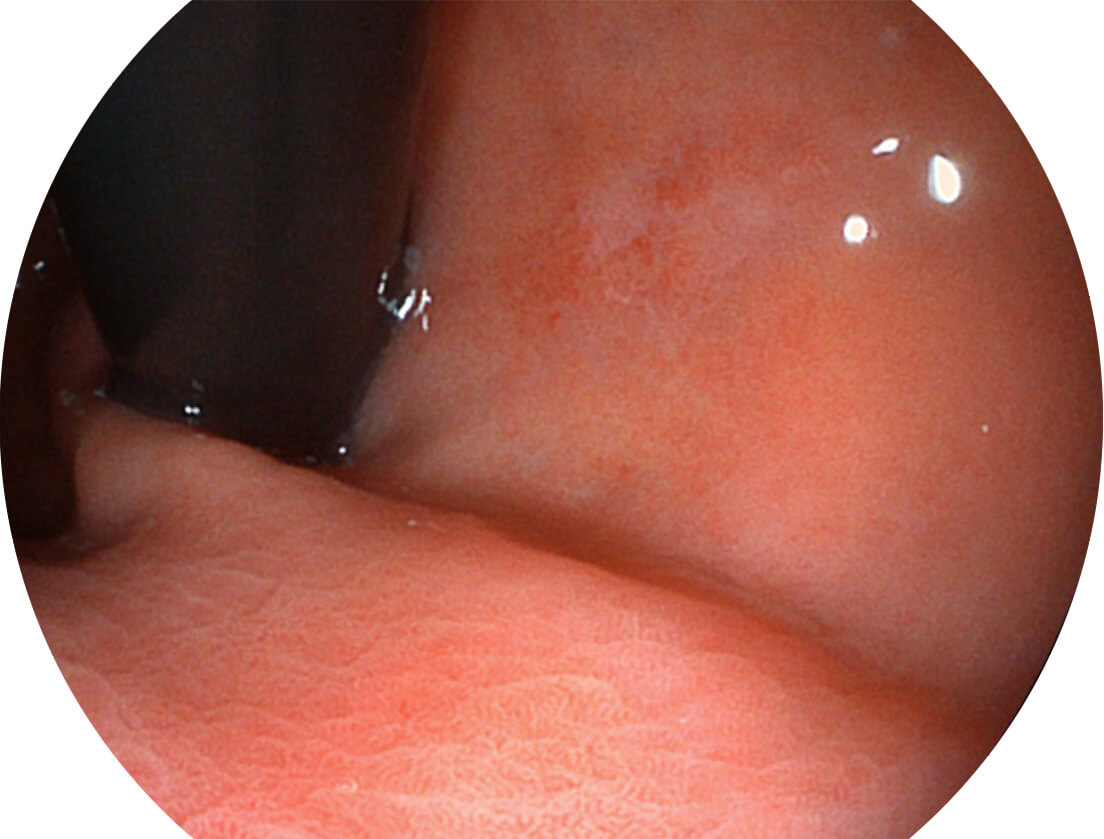

白光图像

SFI图像

图像具有高亮度、高黏膜血管颜色对比度的特点,且不改变粘液、食物残渣、粪便的基本颜色,可在中远景下进行观察,助力消化道早期疾病的诊断。